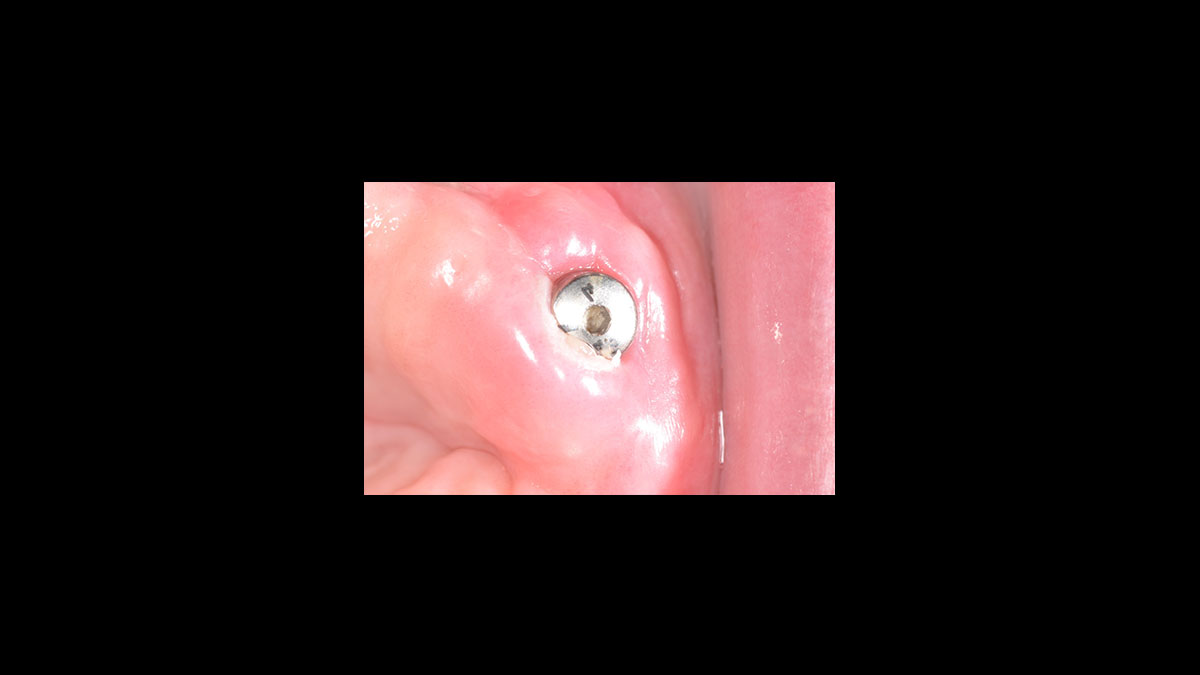

Exposition de l’implant